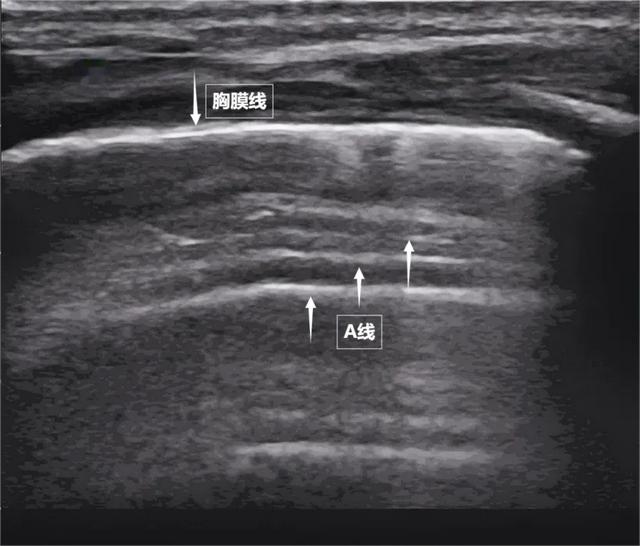

第一景:“海岸线与海浪”——胸膜线与A线当声波穿过胸壁肋骨缝隙,首先会遇到紧贴肺表面的光滑薄膜——壁层胸膜和脏层胸膜。两者紧密相贴,中间没有多余的气体或液体。它们在屏幕上呈现为一条明亮、光滑的水平线,共同构成了胸膜线。这条线就是肺的“海岸线”。在它的下方,由于肺泡内大量气体对声波的强烈反射,会出现一系列与胸膜线平行的、等间距的、重复出现的明亮平行线,像海浪般不断向屏幕深处延伸,这就是A线(见下图)。A线是正常含气肺部的典型标志。它的存在直接提示肺表面含气充足,胸膜腔内无异常积液或气体。